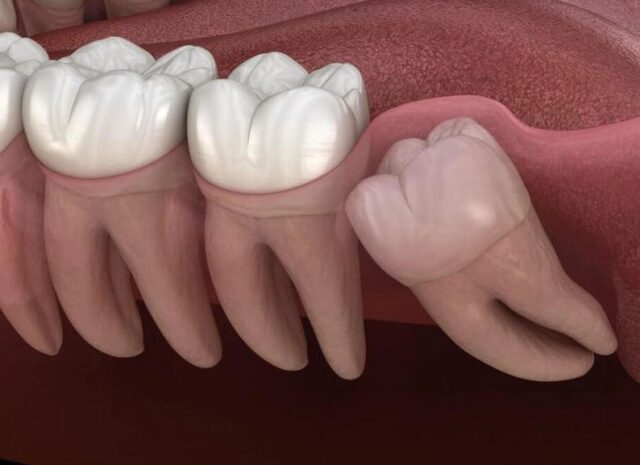

Răng khôn là chiếc răng cuối cùng mọc trên cung hàm của mỗi người. Chúng nằm ở vị trí trong cùng, sau răng số 7 (răng hàm lớn thứ hai).

• Thời điểm mọc: Răng số 8 thường xuất hiện trong độ tuổi từ 17 đến 25, giai đoạn con người đã trưởng thành và được xem là “khôn” hơn, do đó mới có tên gọi là răng khôn.

• Chức năng: Về mặt chức năng ăn nhai, răng số 8 hầu như không đóng vai trò quan trọng, vì các răng hàm trước đã đảm nhiệm tốt vai trò nghiền thức ăn. Chính vì vậy, việc loại bỏ răng khôn mọc lệch, mọc ngầm thường được khuyến nghị.

Răng số 8 dễ mọc ngầm, mọc lệch là do sự khác biệt giữa thời điểm mọc của chúng và quá trình phát triển của hàm.

• Cung hàm không đủ chỗ: Đây là nguyên nhân phổ biến nhất. Khi răng số 8 bắt đầu mọc, toàn bộ các răng khác trên cung hàm đã ổn định vị trí. Nếu xương hàm của bạn có kích thước nhỏ hoặc các răng khác quá lớn, không còn đủ khoảng trống, răng khôn buộc phải tìm đường mọc theo hướng bất thường, dẫn đến mọc nghiêng, mọc lệch hoặc mọc kẹt, mọc ngầm hoàn toàn dưới nướu và xương hàm.

• Xương hàm đã cứng: Ở độ tuổi 17-25, xương hàm đã phát triển hoàn chỉnh và trở nên đặc, cứng. Điều này khiến cho quá trình mọc của răng số 8 gặp nhiều khó khăn hơn so với các răng khác mọc ở giai đoạn trẻ em.

• Yếu tố di truyền: Hình dáng và kích thước xương hàm, cũng như hướng mầm răng ban đầu, có thể bị ảnh hưởng bởi yếu tố di truyền từ cha mẹ.

• Sự cản trở từ răng số 7: Răng 8 mọc ngầm thường gặp sự cản trở từ chân hoặc thân răng số 7 ở phía trước, khiến nó không thể trồi lên đúng vị trí thẳng đứng.